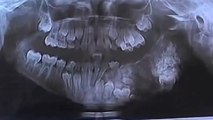

Incroyable ! On lui retire 80 dents de la mâchoire !

Un jeune Indien se fait retirer 80 dents en une seule opération